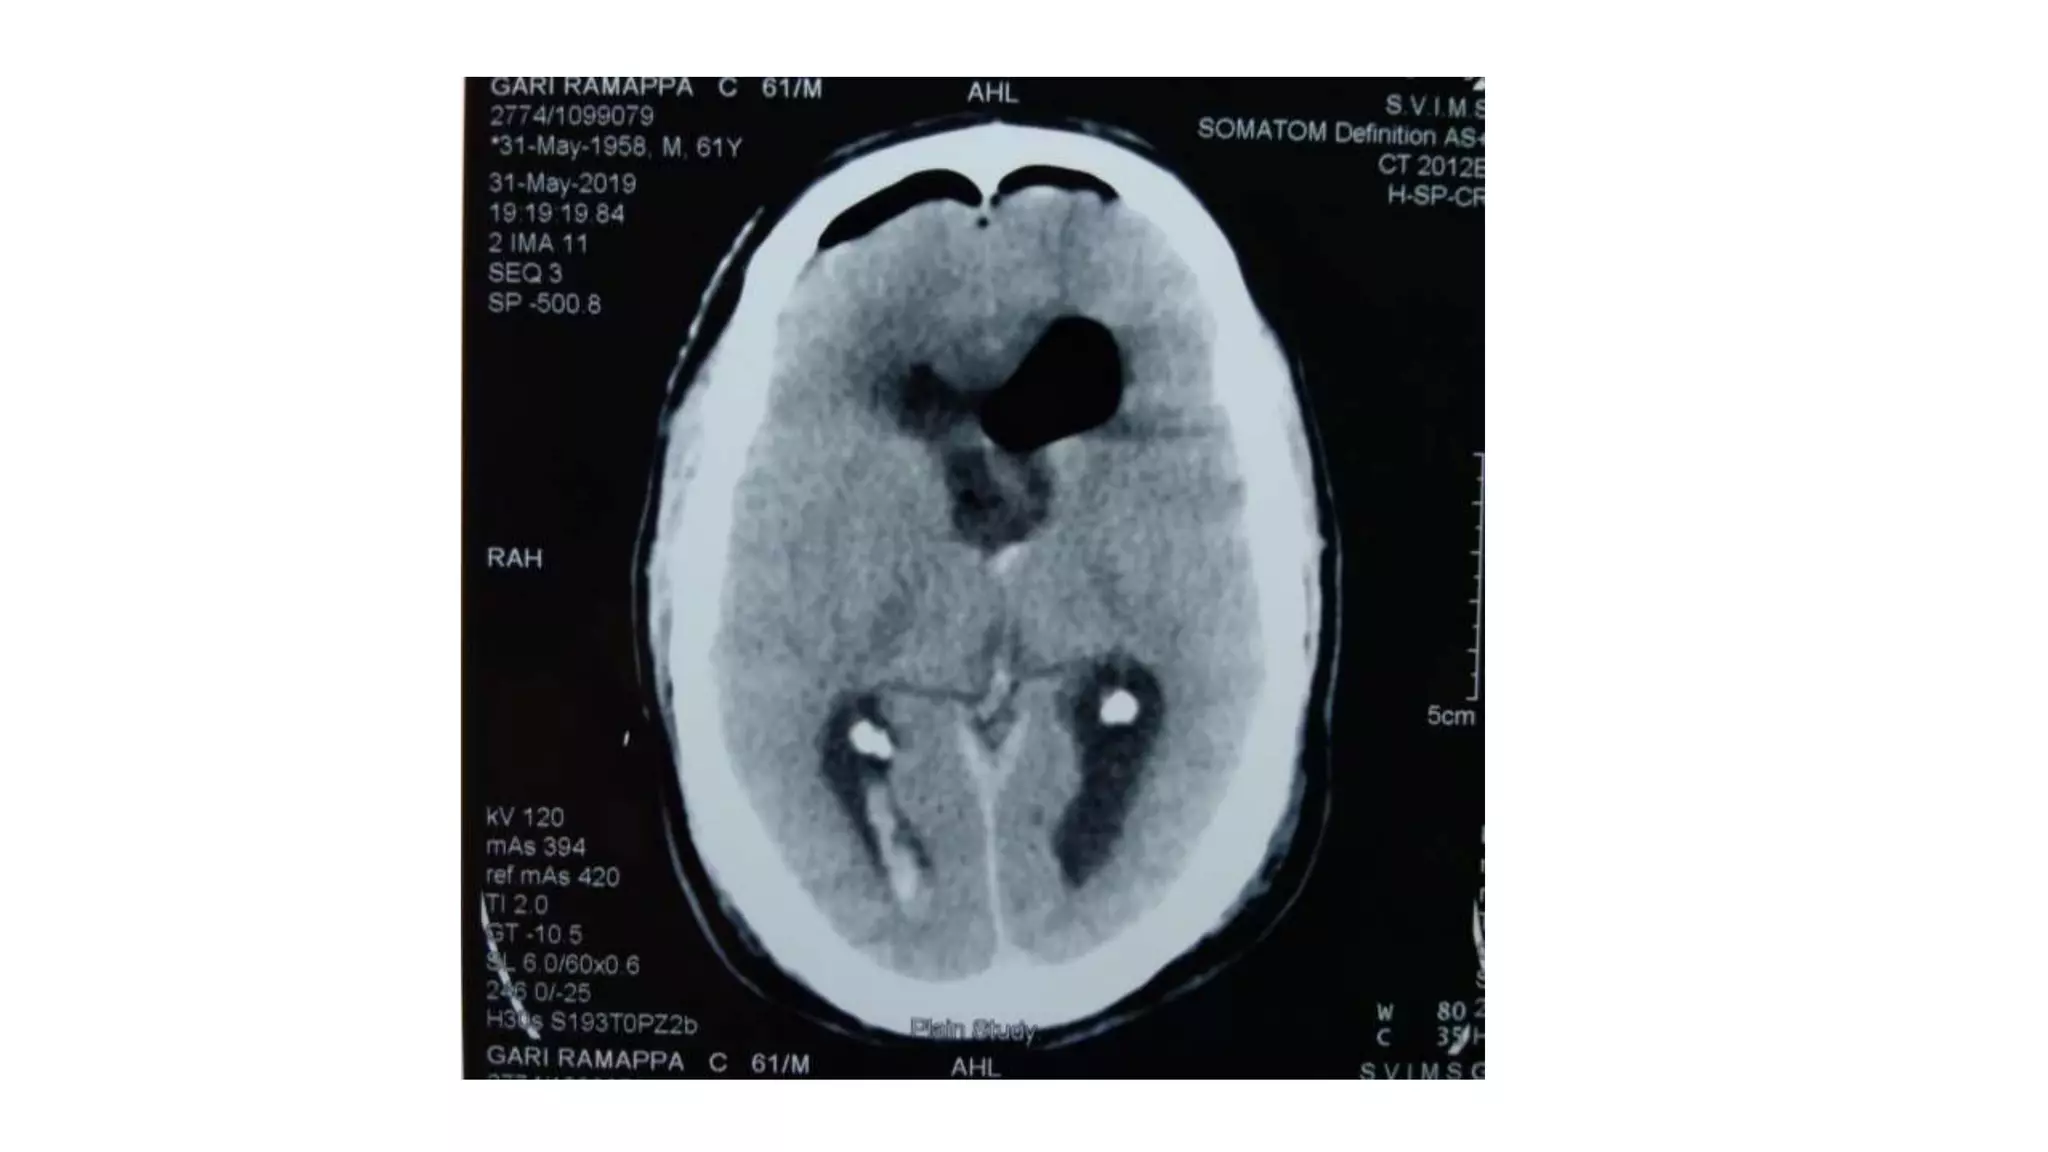

ventriculomegaly

Yes

Trans cortical

no

Trans callosal

• Hydrocephalus more in trans cortical approach

meningitis all in trans cortical approach